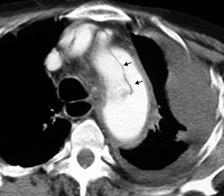

Signo de la Pleura separada “Split pleural sign”

Capas pleurales de grosor uniforme realzadas por el contraste

No específico de empiema. Indica “exudado”. 68% de pacientes con empiema pleural.

Capas pleurales de grosor uniforme

Realce grasa extrapleural (30%)

> Grasa Extrapleural. (60-80%)

Kraus GJ. Split pleural sign. Radiology 2007

Pleural visceral 50%

Pleural parietal 100%